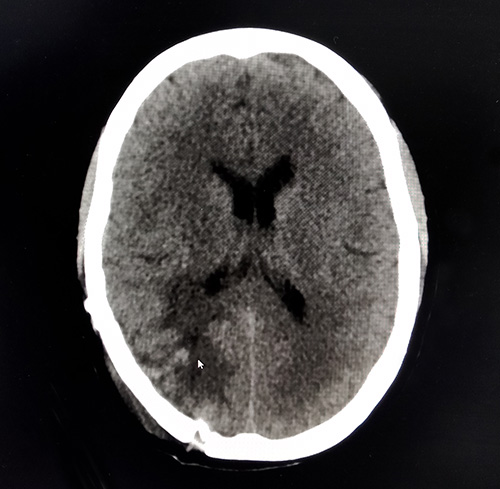

▲术后CT查片已不见肿瘤踪迹

术后,胡女士恢复情况良好。沈教授表示,脑瘤的切除让患者暂时脱离了险境,但仍存在复发的可能。后续通过积极采取化疗、放疗等多模式综合治疗,以此缓解临床症状、减轻痛苦,从而达到患者生命延长、生活质量得以显著提高,所有这些还是可以做到的。